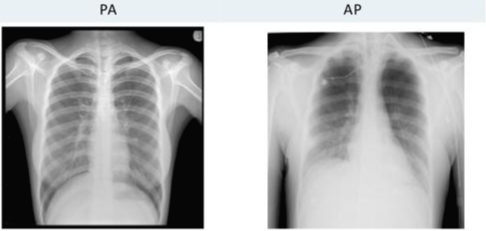

Chest X-ray (CXR)를 찍을 때 찍는 방향에 따라 AP(Anterior-Posterior)와 PA(Posterior-Anterior)로 나눌 수 있습니다.

Chest X-ray의 경우 찍는 방향에 따라 나오는 X-ray 이미지 상태가 다릅니다.

보통, AP 방식으로 찍기보다 PA 방식을 찍는데 그 이유는 아래와 같습니다.

- AP view: 심장이 확대되어 보이며, 견갑골에 의해 폐야가 많이 가려지며, 횡경(Diaphragm)막이 높이 올라가 있어 폐가 좁게 나타남

- 따라서 COVID-19 선별진료소와 같이 Chest AP에서 얻은 CXR 이미지는 폐 병변을 보기에는 사실 썩 좋지 않은 경우가 꽤 있다. (Dataset 수집할 때 이러한 부분도 고려하면 좋을 듯)

- 위의 그림을 보면 같은 환자인데 Chest AP에서는 심장 size도 크고 그리고 견갑골에 의해서 폐야도 많이 가려지는 형태고 그 다음에 diaphragm도 많이 올라와 있기 때문에 PA와 비교했을 때 상당히 폐야가 좁고, 굉장히 내부의 vessel도 굉장히 engorgement(폐에서의 염증성 충혈)되어 보이는 경우가 많습니다.